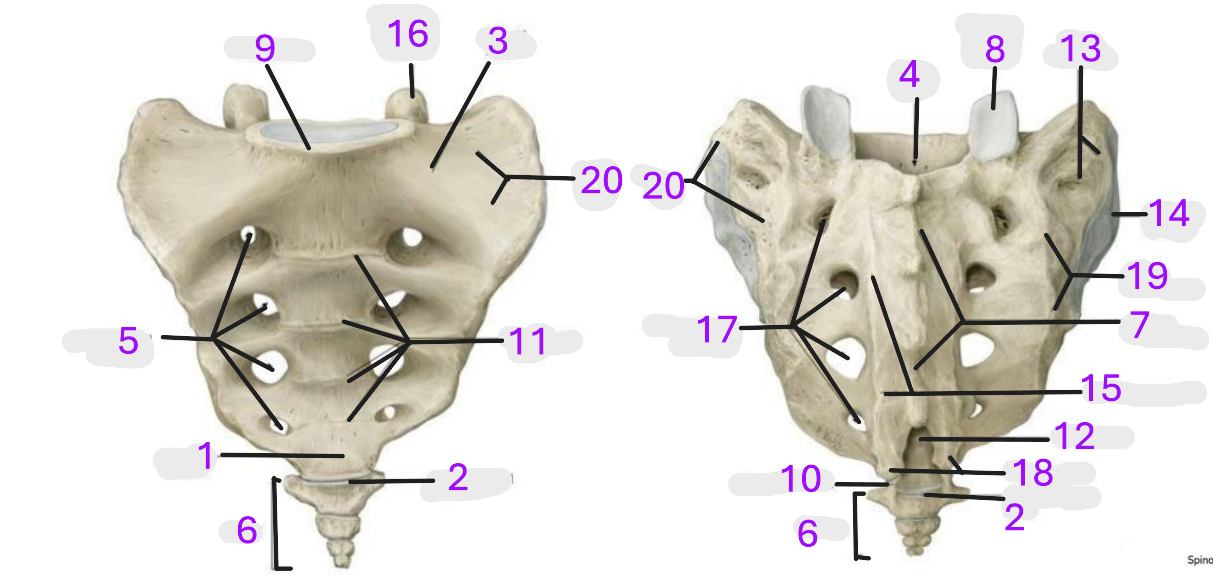

Where is the apex of sacrum

1

Where is the sacrococcygeal joint

2

Where is the wing of sacrum

3

Where is the sacral canal

4

Where is the anterior sacral foramina

5

Where is the coccyx

6

Where is the median sacral crest

7

Where is the superior articular facet

8

Where is the promontory

9

Where is the coccygeal cornu

10

Where is the transverse lines

11

Where is the sacral hiatus

12

Where is the sacral tuberosity

13

Where is the auricular surface

14

Where is the medial sacral crest

15

Where is the superior articular process

16

Where is the posterior sacral foramina

17

Where is the sacral cornua

18